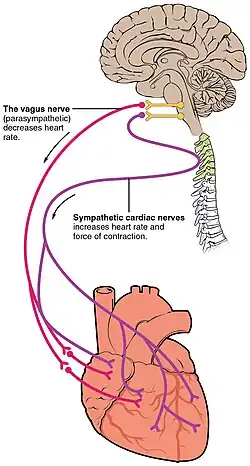

Embora o coração possua o seu próprio sistema excitatório, também é irrigado por nervos do sistema nervoso simpático e parassimpático. Estes nervos não ativam o batimento cardíaco, mas são capazes de influenciar o seu ritmo e força de contração.[35]

O coração recebe sinais nervosos do nervo vago e de nervos no tronco simpático. Estes nervos atuam para influenciar, e não controlar, o ritmo cardíaco. Os nervos simpáticos também influenciam a força da contração cardíaca.[36] Os sinais que são transmitidos por estes nervos têm origem em dois centros cardiovasculares no bulbo raquidiano. O nervo vago do sistema nervoso parassimpático atua para diminuir o ritmo cardíaco, enquanto os nervos do tronco simpático atuam para aumentar o ritmo cardíaco.[7] Estes nervos formam uma rede nervosa em redor do coração denominada plexo cardíaco.[7][37]

O nervo vago é um nervo comprido e sinuoso que tem origem no tronco cerebral e que fornece estímulos parassimpáticos a vários órgãos no tórax e no abdómen, entre os quais o coração.[38] Os nervos do tronco simpático têm origem nos gânglios torácicos T1 a T4 e terminam nos nós sinusais e auriculoventricular, nas aurículas e nos ventrículos. Os ventrículos são mais ricamente inervados por fibras simpáticas do que parassimpáticas. A estimulação simpática provoca a libertação do neurotransmissor noradrenalina na junção neuromuscular dos nervos cardíacos. Isto diminui o período de repolarização, aumentando assim o ritmo de despolarização e contração, o que aumenta o ritmo cardíaco. Abre também os canais iónicos de cálcio e de sódio, permitindo um afluxo de iões de carga positiva.[7] A noradrenalina liga-se ao receptor adrenérgico beta 1.[7]